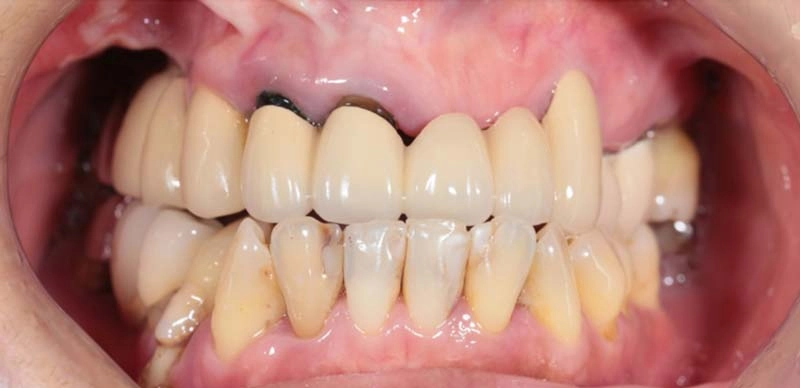

上顎牙橋鬆脫

all on 6全口修復牙齒外觀及功能